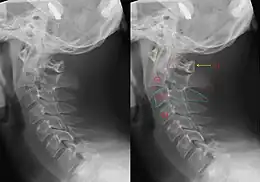

| CT scan of hangman's fracture | |

Hangman's fracture is the colloquial name given to a fracture of both pedicles, or partes interarticulares, of the axis vertebra (C2).[1]